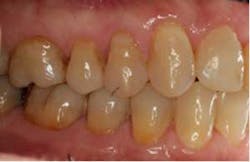

SFOT was used with a high-tech clear aligner to address hard- and soft-tissue deficiencies and severe maxillary and mandibular arch constriction.

Total treatment time: 6 months. Patient declined recommended further clear aligner refinement and fine-tuning periodontal plastic surgery.

Surgically facilitated orthodontic therapy addresses the real, underlying problem of insufficient alveolar bone and expands the traditional “orthodontic walls.” It can reduce the need for extraction therapy, enable more ideal function and esthetics, enlarge arch form, decrease morbidity, increase predictability, enhance long-term stability, and significantly shorten treatment times. These SFOT advantages combined with clear aligner therapy creates a highly acceptable, cost-effective patient option for optimal interdisciplinary care.